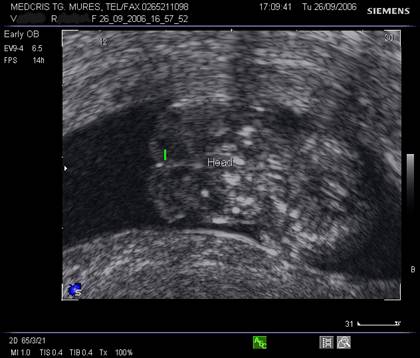

Fig nr.115 Acrania la 11 saptamani. Linia indica plexurile choroide, fara invelisul calotei craniene, la ecografia transvaginala

Fig. nr.116. Craniu fetal la 12 sapt. Se remarca prezenta calotei craniene (sageata) in jurul plexurilor choroide